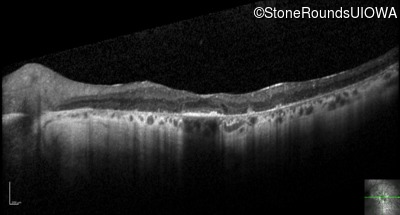

Optical Coherence Tomography - Left - 20/70 +1

Exemplar / OCT Stack